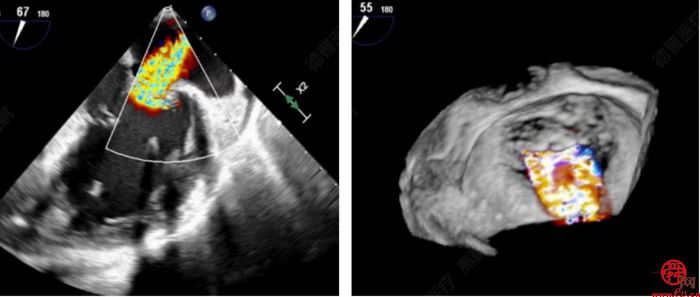

术中,患者全麻后,在经食道超声和DSA的引导下,经股静脉建立路径,穿刺房间隔,瓣膜夹通过输送系统送入左心房,顺利到达二尖瓣病变区域。在经食道超声和DSA的辅助下,术者通过反复评估二尖瓣反流位置、抓捕位置、反流程度、巧妙夹合,在A2/P2区植入2枚DragonFly夹子。术后,患者反流程度从4+转至1+,手术取得成功。

术前经胸心脏彩超和经食道超声提示:二尖瓣重度反流4+,反流束宽度=18.6mm,缩流颈宽度VC=0.8cm,有效反流口面积(EROA)=0.74,二尖瓣瓣口面积4.510cm。

安贵鹏手术团队术前组织了讨论,对手术适应证,术中可能出现的并发症和应对策略进行了全面分析。经专家充分评估,决定实施经导管二尖瓣缘对缘修复术。患者为功能性二尖瓣反流(FMR)Ⅲb型,基线期MR4+,反流束宽度=18.6mm反流位于2区且累及1区和3区;为保证反流程度有效降低,需要在2区植入两枚宽瓣膜夹。后叶有假腱索,瓣叶捞取有困难,因此手术存在较多挑战。